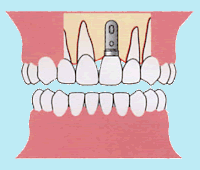

簡単に言うと、インプラント治療は、チタン製の人工の歯根を顎の骨に埋め込み、その上部に人工歯を被せる治療法です。

やはりインプラント治療の一番の特徴は、まわりのほかの歯に余分な負担をかけたり、傷けずにすむということです。